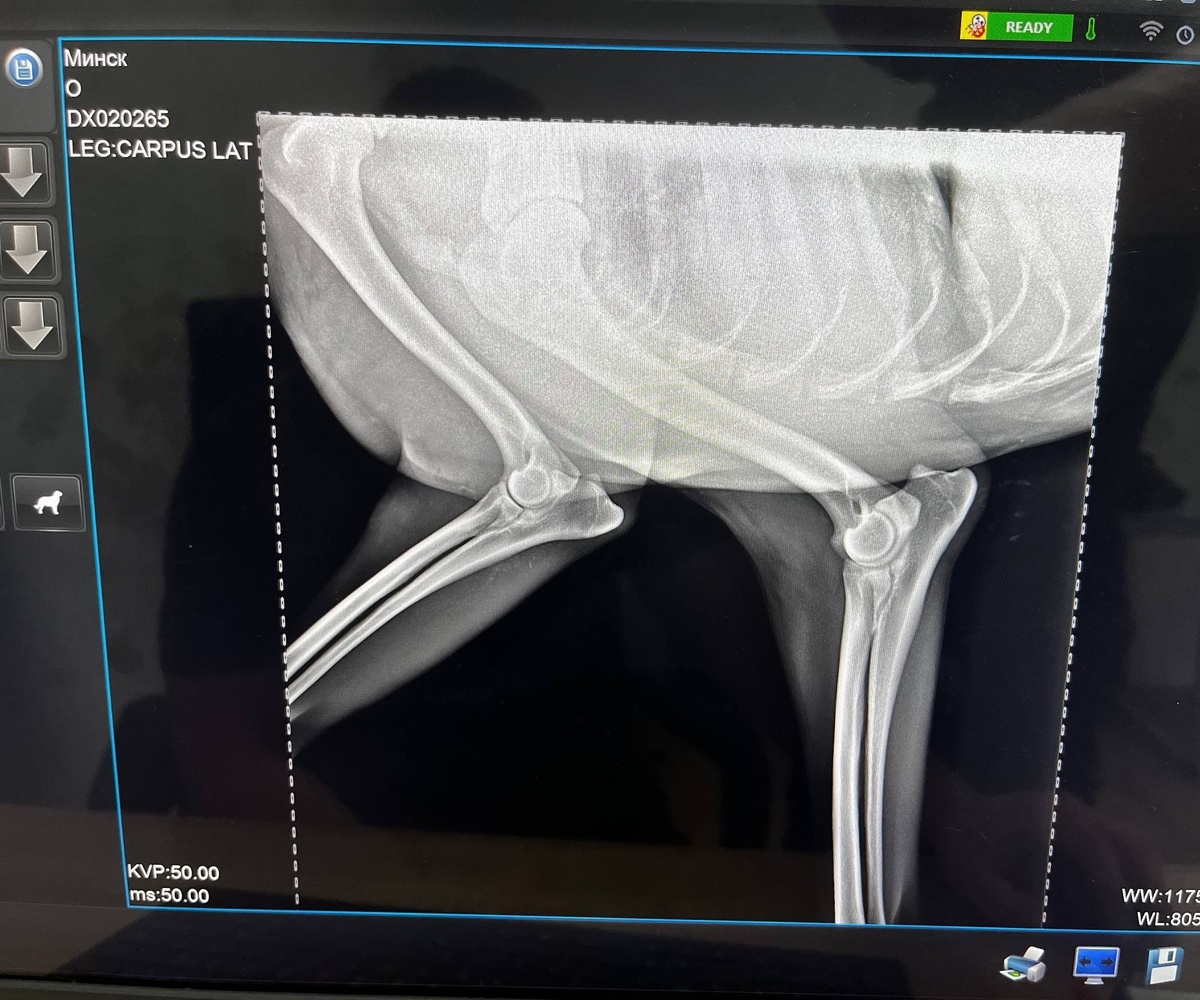

В районе Ленинского пути прохожие обнаружили собаку, которая прыгала на трех лапах, пыталась спрятаться под грузовиком и скулила от боли. За помощью неравнодушные люди обратились в ивановский приют «Майский день».

На место выехал кинолог, который доставил животное в ветклинику. Осмотр показал: у собаки сильный ушиб передней лапы и множественные ссадины. Вероятно, она попала под колеса.